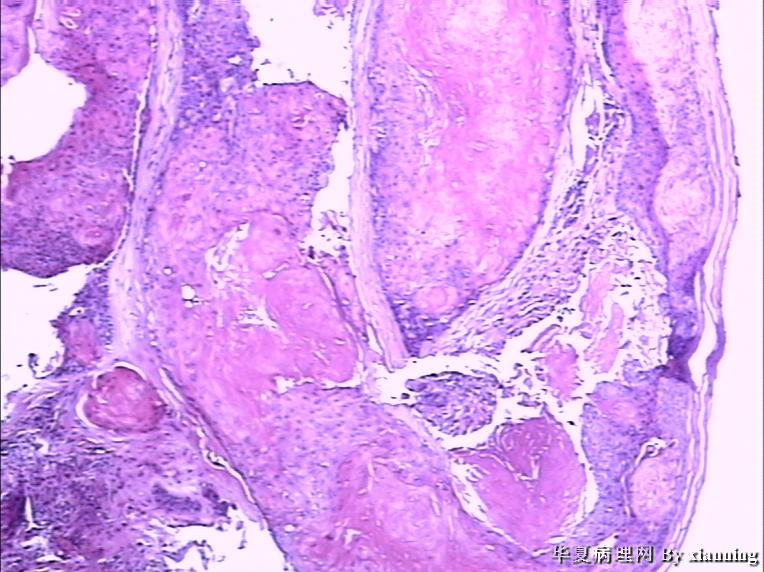

女 50岁 头皮下肿块

巨检:灰白色不规则结节0.9*0.7*0.4cm3,切面灰白色实性质地中等

名称:图3

描述:36580005